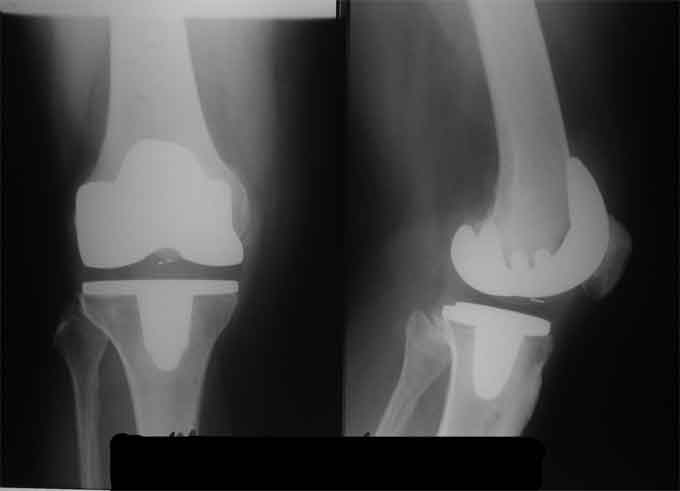

Оперирована пациентка 42 лет, избыточного веса. Выполнено б/ц протезированние коленного сустава эндопротезом LCS. Послеоперационный период гладкий, в срок 2 мес. после операции объем движений удовлетворительный, сгибание до острого угла, разгибание полное. В 3,5 мес. во время падения подвернула ногу, после чего появилась. клиника медиолатеральной нестабильности. В течении 3 недель фиксация в туторе. При повторном осмотре жалобы на дискомфорт в коленном суставе, «щелканье», неустойчивость в суставе. Вопросы/варианты дальнейшей тактики лечения пациентки.

1) Существует ли способы восстановления внутренней боковой связки на фоне протезированного коленного сустава и как добиться равномерного ее натяжения при всех углах сгибания.

2) Ревизия с установкой более связанного протеза (constrained)